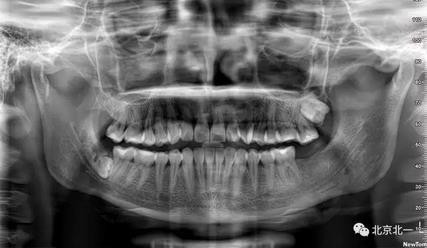

病例資料:一般情況,患者女性,28歲, 主訴:要求拔右側下頜智齒,檢查:右側下頜第三磨牙未見萌出, 拍片如圖。

圖一:CBCT顯示右側下頜水平骨埋伏牙,牙冠距離下牙槽神經(jīng)管接近。

圖二:自帶的CBCT顯示下牙槽神經(jīng)管貼著智齒走形。